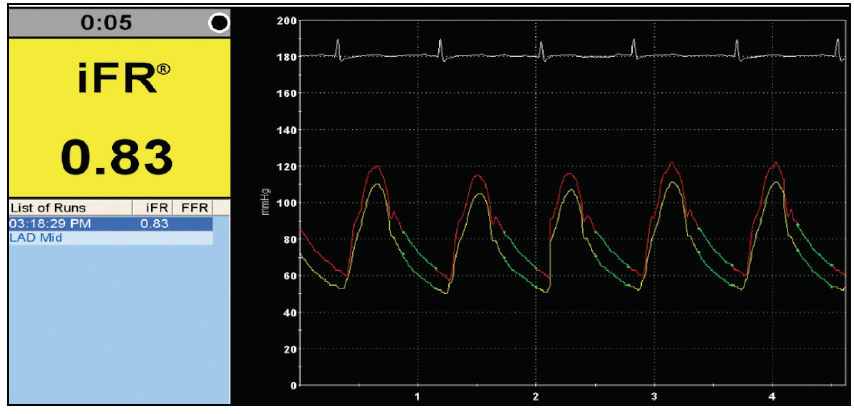

A new option for intravascular physiologic assessment appears to be iFR, which has the advantage of not requiring vasodilation and, similar to FFR, helps reclassify and convert from PCI to optimal medical management.33 The cutoff point for iFR is 0.89 (Figure 3).